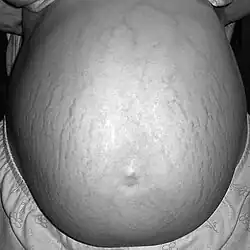

![]() Estrías abdominales. | ||

Striae gravidarum en embarazada, dos semanas antes del parto.